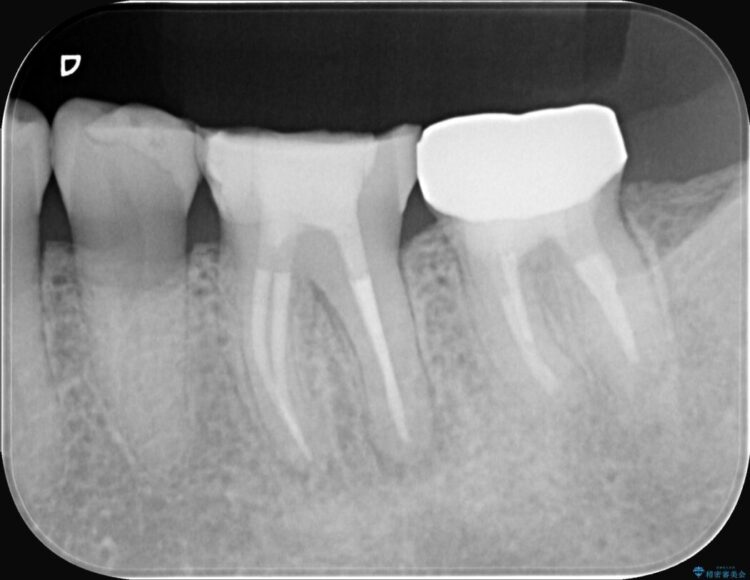

レントゲンを確認すると、歯髄腔が狭くなり根管が石灰化している難症例でした。

患者様の大切な歯を残すため、歯科用顕微鏡を用いた精密根管治療を行うことで、狭く、見えにくい根管を正確に探し出し、治療を完了させる計画を立案しました。

今回の治療は、特に難易度の高い石灰化した根管が対象でした。

まず、治療中の細菌感染を防ぐためにラバーダムを使用。次に、歯科用顕微鏡で治療部位を何十倍にも拡大しながら、狭窄した根管の入り口を探し、慎重に拡大・清掃を行いました。顕微鏡を用いることで、肉眼では不可能だった根管内部の細かい構造を確認しながら、感染源を徹底的に除去することができました。これにより、難症例の奥歯でも再発リスクを抑えた適切な処置を行うことができ、治療後に痛みは解消。大切な歯を長期間にわたり保存することができました。